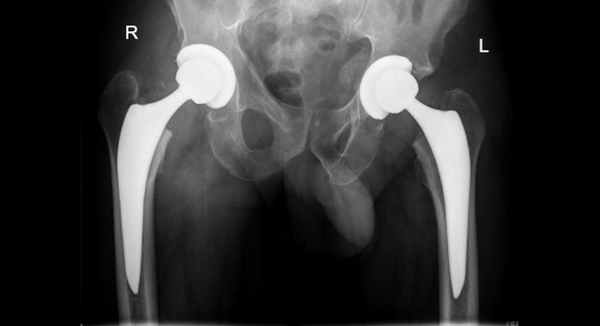

Особенно трудную задачу представляет лечение переломов у пациентов с остеопорозом. Перелом бывает настолько раздробленным, а состояние костной ткани настолько измененным, что использование обычных методов фиксации обречено на неудачу. В таких случаях проводят тотальное эндопротезирование тазобедренного сустава.

Тазовый компонент протеза обеспечивает улучшение фиксации перелома и делает возможной раннюю нагрузку на ногу у людей пожилого возраста. Поскольку при тотальном эндопротезировании головку бедренной кости отсекают, расширенные и комбинированные доступы могут не потребоваться, что, возможно, будет способствовать уменьшению последствий хирургического вмешательства.

- Эндопротезирование. Заключается в полной замене поврежденной части или всего тазобедренного сустава искусственным аналогом.